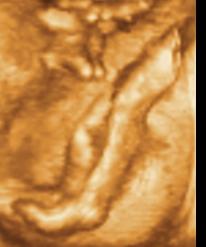

Ui.: Kedden megyünk genetikai UH-ra, szorítsatok nekem. Aztán majd jelentkezem.